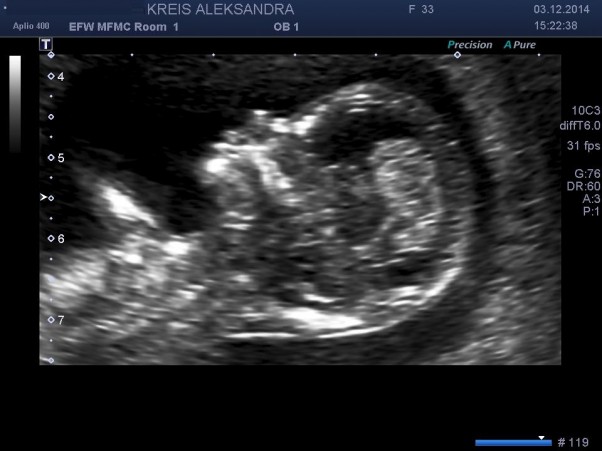

USG przeziernosc karkowa

13 tydz, idziemy na badania by upewnic sie ze wszystko jest wporzadku.